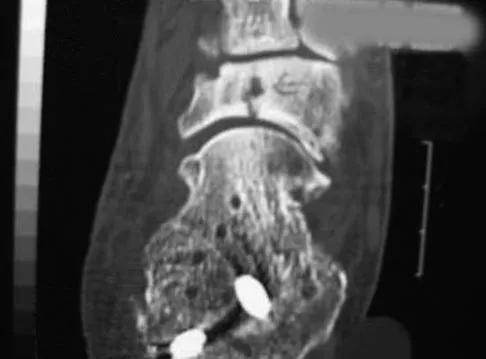

A 19-year-old man has had pain and swelling in his left forearm for the past 8 months. Laboratory studies show a mildly elevated WBC count and erythrocyte sedimentation rate. Radiographs are shown in Figures 58a and 58b, a CT scan is shown in Figure 58c, and T1- and T2-weighted MRI scans are shown in Figures 58d and 58e, respectively. A biopsy specimen is shown in Figure 58f. Immunohistochemistry demonstrates that the lesion is negative for leukocyte common antigen (CD34). What is the most common cytogenetic translocation associated with this lesion?

Explanation

The imaging studies show a permeative lytic destructive lesion in the proximal radius with "hair-on-end" periosteal reaction and a large soft-tissue mass most consistent with Ewing's sarcoma. The pathology reveals monotonous sheets of "round blue" cells. This limits the differential diagnosis to primary lymphoma of bone versus Ewing's sarcoma. These are best differentiated by immunohistochemistry, cytogenetics, and flow cytometry. Lymphoma of bone is typically CD34 positive and CD99 negative; whereas, the reverse is true of Ewing's sarcoma, CD34 negative and CD99 positive. The most common cytogenetic translocation with Ewing's sarcoma is 11; 22; 21; 22 and 7; 22 translocations have also been reported in Ewing's sarcomas. The X; 18 translocation is most commonly associated with synovial cell sarcomas; the 12; 22 translocation is most commonly associated with clear cell sarcomas; the 2; 13 translocation is most commonly associated with alveolar rhabdomyosarcomas, and the 12; 16 translocation is most commonly associated with myxoid liposarcomas. Flow cytometry is used to characterize the cell types of lymphomas. Womer R: The cellular biology of bone tumors. Clin Orthop Relat Res 1991;262:12-21. Yamaguchi U, Hasegawa T, Morimoto Y, et al: A practical approach to the clinical diagnosis of Ewing's sarcoma/primitive neuroectodermal tumour and other small round cell tumours sharing EWS rearrangement using new fluorescence in situ hybridisation probes for EWSR1 on formalin fixed, paraffin wax embedded tissue. J Clin Pathol 2005;58:1051-1056.